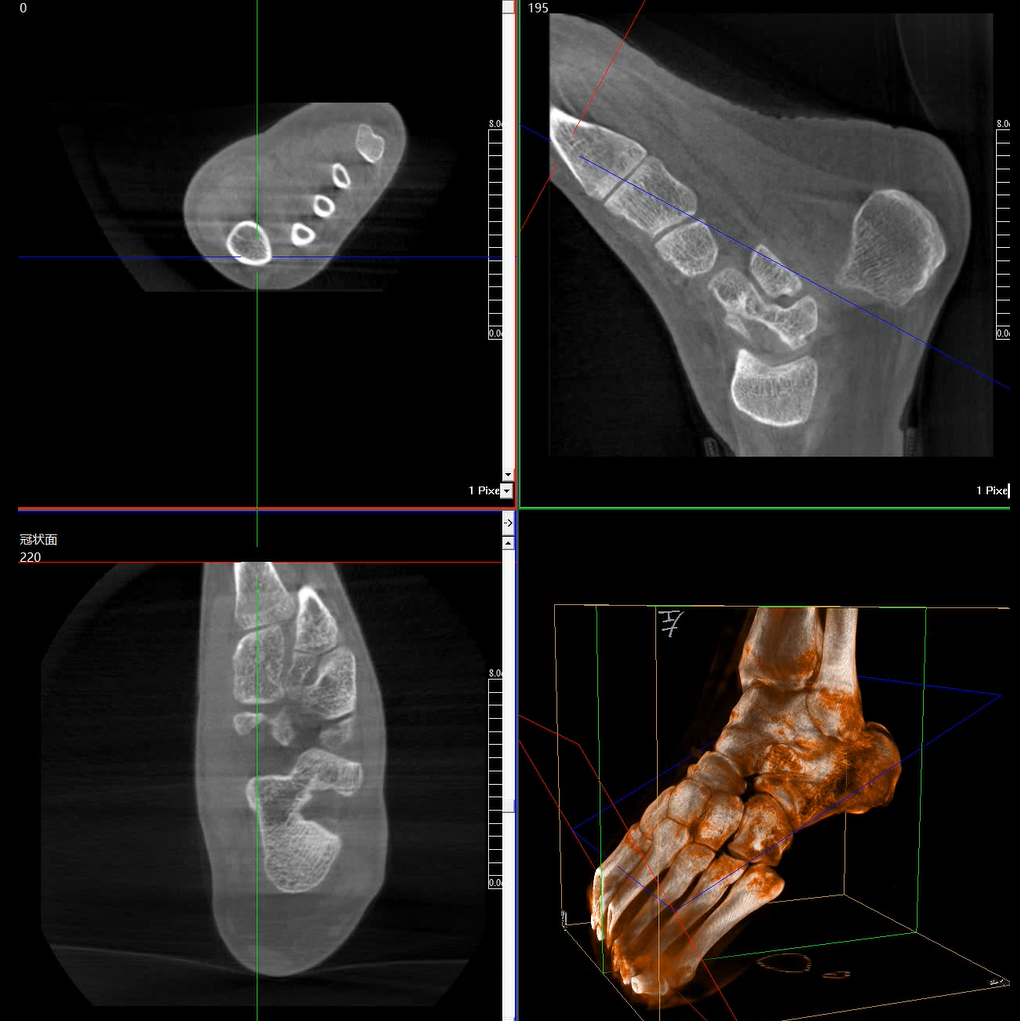

術中三維成像和橫斷面圖像提供多角度的手術診斷信息,輔助醫生進行術中評估判斷,諸如骨折復位情況和內植入螺釘的尺寸和位置,輔助手術更好地完成。

提供更大的術中三維成像視野,采集更多圖像信息,可一次拍全全段頸椎、全段腰椎、七節胸椎、雙側骶髂關節、股骨頭及單側盆骨。

在C臂掃描過程中,始終保持拍攝主體處于射線束的中心,避免了序列圖像采集過程中的橫縱方向運動,減少相對運動造成的運動偽影。

平板垂直升降運動 便于術中微調平板與拍攝主體的距離,更加貼近病灶體,成像范圍更大,圖像更清晰。